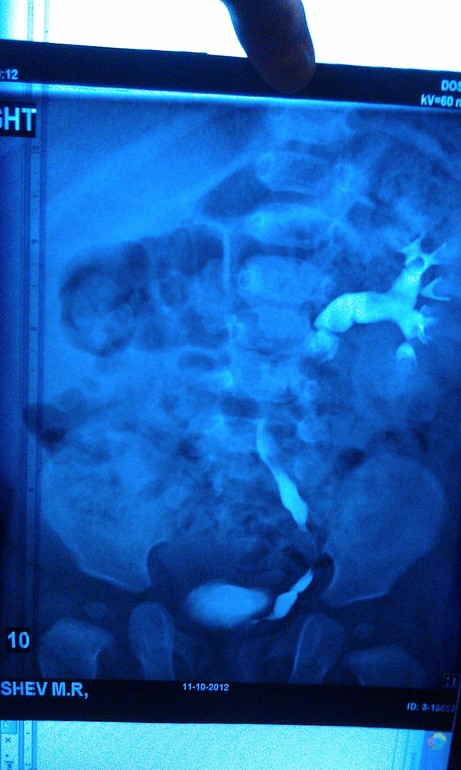

Олеся, не имея снимков в руках я не могу ручаться за какие то увиденные нюансы, разрешение не то. Справа есть тень, но тень это кишечника или тазовая дистопия почки я понять не могу. Слева гидронефроз это понятно, но вам только экскреторной урографии недостаточно для обследования. Надо делать цистографию, что бы исключить рефлюксирующий мегауретер, а для выяснения функции правой почки надо делать нефросцинтиграфию. Но это мое субъективное мнение, без знания ситуации сложно говорить о чем то определенно